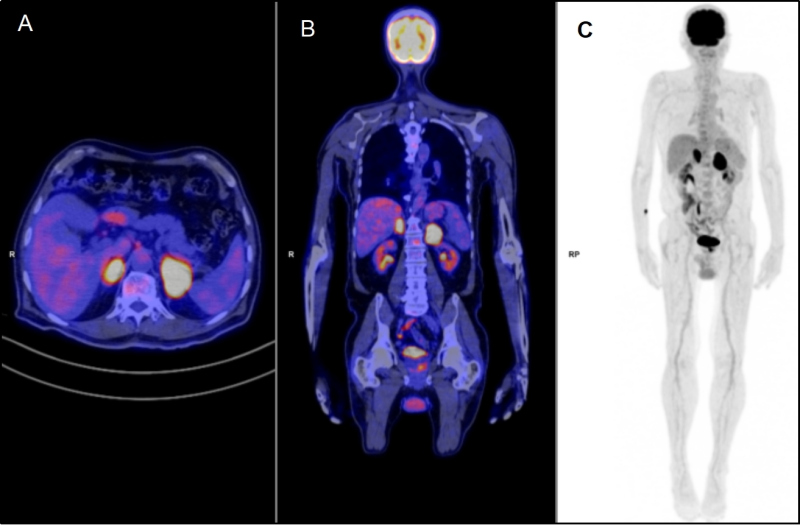

Con el fin de estadificar y caracterizar el comportamiento metabólico de las lesiones descritas en las glándulas suprarrenales, se realizó un estudio 18F-FDG PET/TC que mostró masas adrenales sólidas bilaterales con intenso aumento del metabolismo, sin evidencia de compromiso nodal o extranodal local ni a distancia, compatible con viabilidad tumoral mal diferenciada primaria adrenal bilateral (fig. 3). Dada la ubicación de las masas y sus características por imagen multimodal, se sugirió un diagnóstico de síndrome linfoproliferativo y por decisión multidisciplinaria se realizó adrenalectomía izquierda, cuyo análisis histopatológico e inmunohistoquímico fue compatible con LNH primario adrenal tipo B difuso de células grandes, patrón no-centro germinal (fig. 4).